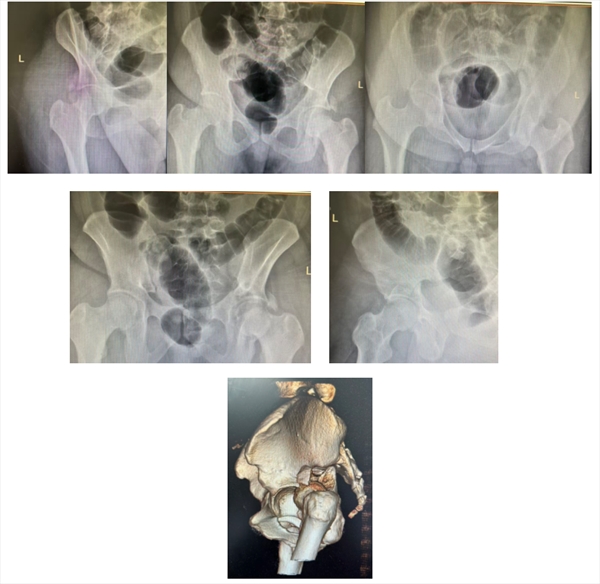

患者小曹(化名),年仅26岁,体重达240斤,因车祸被紧急送至望京医院。经检查,被诊断为极为复杂的“髋臼T型骨折伴股骨头脱位”。

髋臼,是骨盆侧壁那个精密的碗状凹陷,它与股骨头共同构成承载人体上半身重量的核心“承重轴碗”。此类骨折多由车祸、高处坠落等高能量暴力导致,股骨头像一把“重锤”,瞬间将这个“碗”砸碎。在骨科领域,国际上普遍采用Judet-Letournel分型来评估其复杂性,而“T型骨折” 正是其中最复杂、最难处理的类型之一——仿佛这个承重碗先被横着砍裂,再被竖着劈开,形成一道残酷的“T”形裂痕,整个结构分崩离析,稳定性尽失。

(入院时术前X线及CT三维重建结果:髋臼骨折伴脱位)

然而,更为揪心的情况出现了。三维CT检查结果显示,一处锋利如刃的骨折断端,竟紧紧贴附于至关重要的“臀上动脉”下方,甚至部分位于其上。这无疑是在患者体内埋下了一颗“不定时炸弹”,任何细微的移位,都极有可能刺破血管,进而引发致命性的盆腔大出血,严重威胁患者生命。